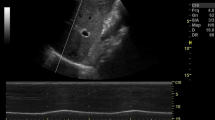

Tidal ventilation at quiet breathing: Initially, the volunteers were asked to breathe quietly to allow the operator to identify the “bat sign” and achieve the correct angle of insonation (Fig. 1A).

Mueller maneuver (Fig. 1B): Subjects were asked to expire forcibly through the mouth, after exhalation of normal tidal volume, to residual volume and to maintain it with a clipped nose. As soon as ultrasound imaging was stabilized, the volunteers performed a sustained maximal inspiratory effort while their mouth closed and nose clipped (Mueller maneuver).

Valsalva maneuver (Fig. 1C): Subjects were asked to inspire rapidly close to total lung capacity and maintain this volume actively for 2–3 s; then, they performed a sustained maximal expiratory effort while their mouth closed and nose clipped (Valsalva maneuver).

False lung sliding during Muller and Valsalva maneuvers. A Placing the probe perpendicular to two consecutive ribs in the parasternal area allowing visualization of the so-called “bat sign”: the upper and lower ribs are the wings of the bat, and, a little deeper, the pleural line is the body of the bat. B False lung sliding during Muller’s maneuver. M-mode imaging reproducing artifacts mimicking lung sliding which is generated by contractions of parasternal intercostal muscles during Muller’s maneuver. C False lung sliding during Valsalva’s maneuver. M-mode imaging reproducing artifacts mimicking lung sliding which is generated by contractions of parasternal intercostal muscles during the Valsalva maneuver

The MyLab Five Esaote Ultrasound System (Esaote SpA, Genoa, Italy) was used, equipped with a high frequency 4–13 MHz broadband linear probe, well suited for sonographic examination of pleural line and parasternal intercostal muscles.

Imaging acquisition was obtained by placing the probe longitudinally along the midclavicular line and perpendicular to two consecutive ribs, at the level of the 3rd to the 4th intercostal spaces. This scan offers a good view of the ribs, intercostal muscles, and pleural lines (Fig. 1A). When the correct position of the probe with proper image acquisition was achieved, the operator registered and saved a 10-s video clip in B-mode for each side and two sequences of six consecutive breaths in M-mode during each respiratory maneuver. Videotapes and images were all stored on a memory disc by the principal investigator (D. G. B.).

Data from the present study showed that the three raters reported lung sliding in most sonographic imaging obtained during Valsalva and Muller maneuvers, in which glottis and nose closure prevented the air from entering the lungs (Table 1). For this reason, during Valsalva and Muller maneuvers, the visceral pleura does not slide over the parietal pleura, as no air enters the lungs. Therefore, sonographic lung sliding should not be visualized in a healthy subject performing Muller or Valsalva maneuvers. The prolonged and maximal contraction of respiratory muscles performed during the maneuvers may explain these findings. The presence of artifacts mimicking lung sliding and produced by the contraction of parasternal intercostal muscles has been previously described in a case series of eight ICU patients after pneumonectomy. In this case series, artifacts were present during spontaneous breathing but were absent during mechanical ventilation under apneic sedation [12, 14]. Similar artifacts may occur in patients suffering from dyspnea [13,14,15]. Both recently pneumonectomized patients and dyspneic patients may share an increased activity of the parasternal intercostal muscles, whose contraction stabilizes the rib cage and contributes to inspiration by moving against a pleural pressure gradient in opposition to the deflationary action of the diaphragm [16, 17, 19]. Our findings allow to clarify the mechanisms originating these artifacts. In fact, by varying the width of intercostal spaces, the active contraction of intercostal muscles during Muller and Valsalva maneuvers may make the parietal pleura move falsely by dragging. This phenomenon may have significant implications for LUS examination in clinical practice. In fact, in patients recruiting intercostal accessory muscles due to respiratory distress, artifacts mimicking lung sliding (Fig. 1B–C) may erroneously lead clinicians to rule out an eventual PNX.

In our study, artifacts induced by the maximal muscular activity performed during Valsalva and Muller maneuvers, as during hyperventilation trials, may have hidden lung pulse in most videos and images (Fig. 1B–C). Finally, the recognition of the sonographic lung sliding may be insufficient to exclude an eventual PNX if substantial intercostal muscle activation is detected on clinical examination or by ultrasound. However, these findings should be interpreted cautiously since Cohen’s k pointed out only a slight to fair inter-rater agreement for Muller and Valsalva maneuvers.